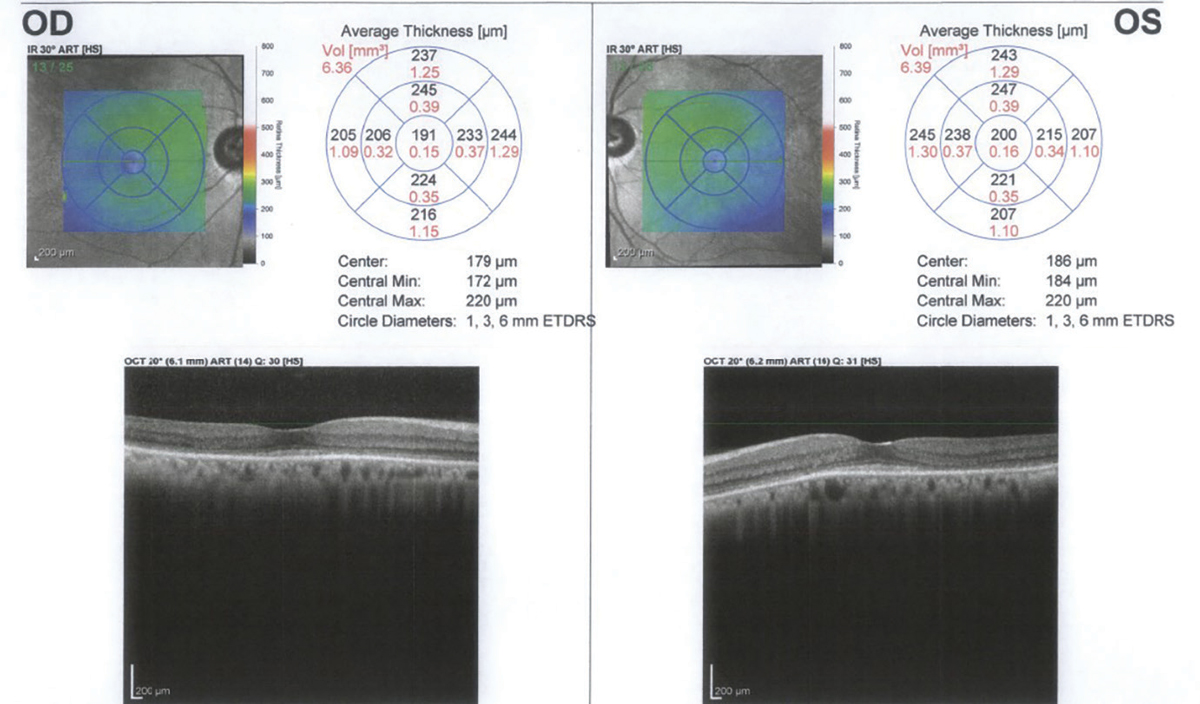

Unilateral Plaquenil Toxicity March 2021 Illinois Retina Associates

Unilateral Plaquenil Toxicity March 2021 Illinois Retina Associates What Does Plaquenil Toxicity Look Like On Oct It can find retinal damage from plaquenil. The test measures how well these cells respond to light. Subtle but characteristic alterations on oct are often your first clue. Plaquenil toxicity is typically asymptomatic in early stages, but over time can lead to severe vision loss and retinal damage. Hydroxychloroquine is frequently used in the treatment of systemic autoimmune and inflammatory. What Does Plaquenil Toxicity Look Like On Oct.

Asymptomatic and Early Hydroxychloroquine Retinal Toxicity noted on OCT What Does Plaquenil Toxicity Look Like On Oct Subtle but characteristic alterations on oct are often your first clue. Chloroquine (cq) and hydroxychloroquine (plaquenil) (hcq) have been used for. The test measures how well these cells respond to light. Spotting the telltale signs of plaquenil toxicity. This test looks at cells in the retina called rods and cones. Your ophthalmologist can use this image to look for early. What Does Plaquenil Toxicity Look Like On Oct.